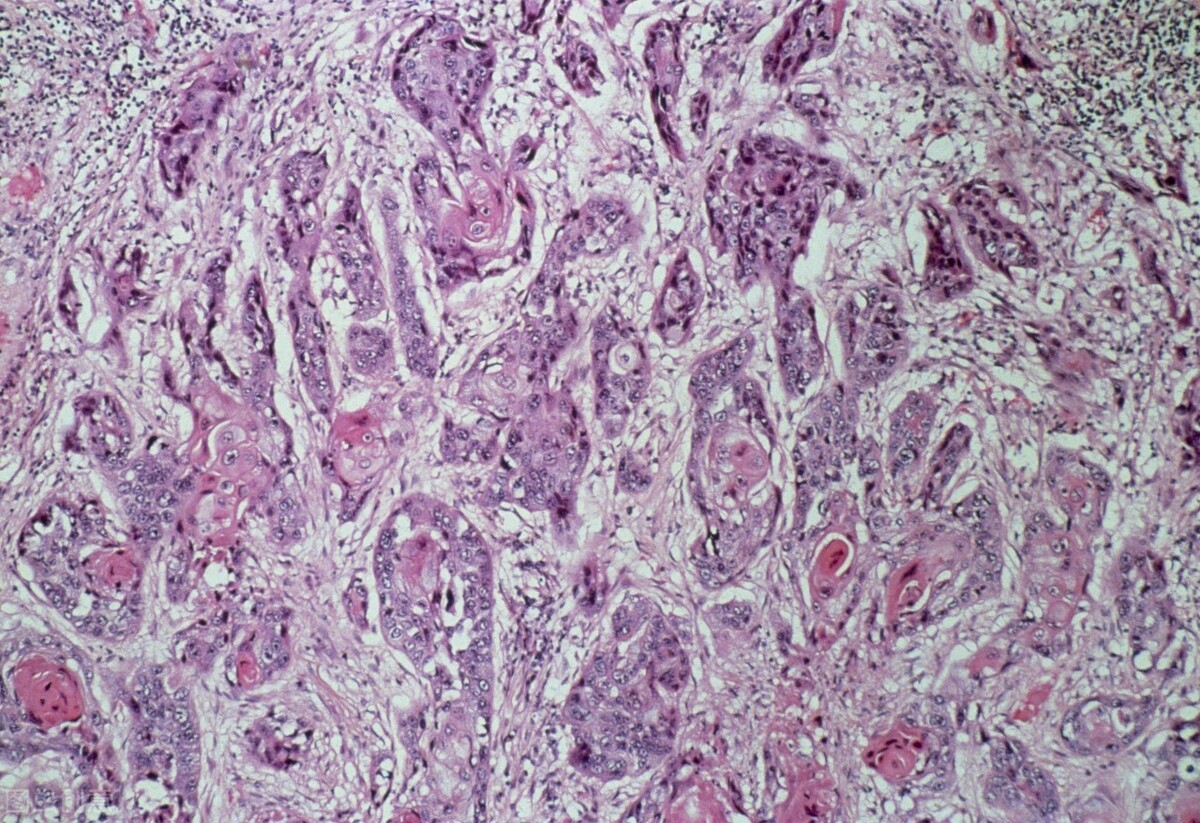

吕先生今年42岁,在2021年秋天开始咳嗽,当时并没有在意,直到两个月前,突然觉得胸痛,甚至出现咯血的现象。到医院活检的结果是肺鳞癌。

肺鳞癌无法完全治愈,只能尽量延长病人生存期。在全世界的全部恶性肿瘤死亡病例中,肺癌占19%,居恶性肿瘤死因的首位。肺癌分为小细胞肺癌和非小细胞肺癌,非小细胞肺癌(其中就包括了肺鳞癌、肺腺癌等)手术治疗,术后化疗或化放疗5年生存率为27%,中位生存时间24个月,其中一期、二期病人,5年生存率为38%。

肺鳞癌的位置多数为中央型,通常会容易压迫到气管及大血管,故会出现胸闷、气喘等症状,若肿块生长的速度较快,很容易引起血管破裂、出现刺激性干咳、咯血或痰中带血的情况,也会有少数患者出现背部疼痛,出现这些症状时,应尽快去医院检查。